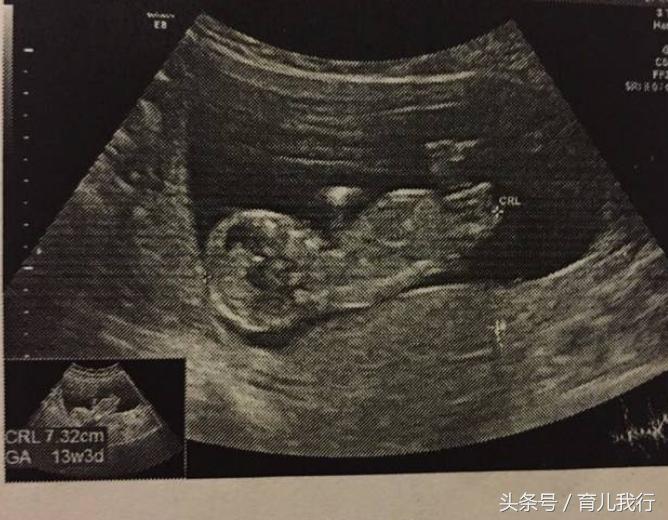

四个月的时候就感受到了第一次的胎动,但是力度还不算大,右边动的次数多一些。40天的孕囊是呈长条形的,这个在我身上就不靠谱了,虽然我检查出的是长条形,但我怀的确是女儿。